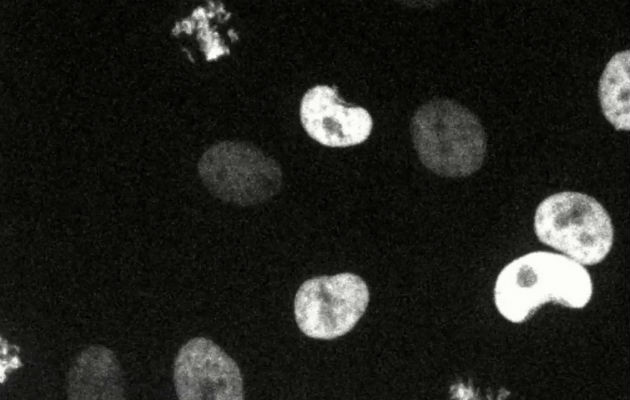

Medicinas que atacan unos genes en células cancerosas podrían errar con otros. Foto/ A. Lin et al., Science Translational Medicine, 2019.

En ciertas formas de la enfermedad, las células cancerosas producen altos niveles de una proteína llamada MELK. Estudios anteriores habían arrojado que MELK era esencial para la propagación del cáncer, y los investigadores ya estaban probando un medicamento para el cáncer de mama que tiene en la mira a esa proteína.

El equipo de Sheltzer utilizó Crispr, una herramienta de edición de ADN, para escindir el gen MELK en células cancerosas. Las células deberían haber dejado de crecer, pero no lo hicieron.